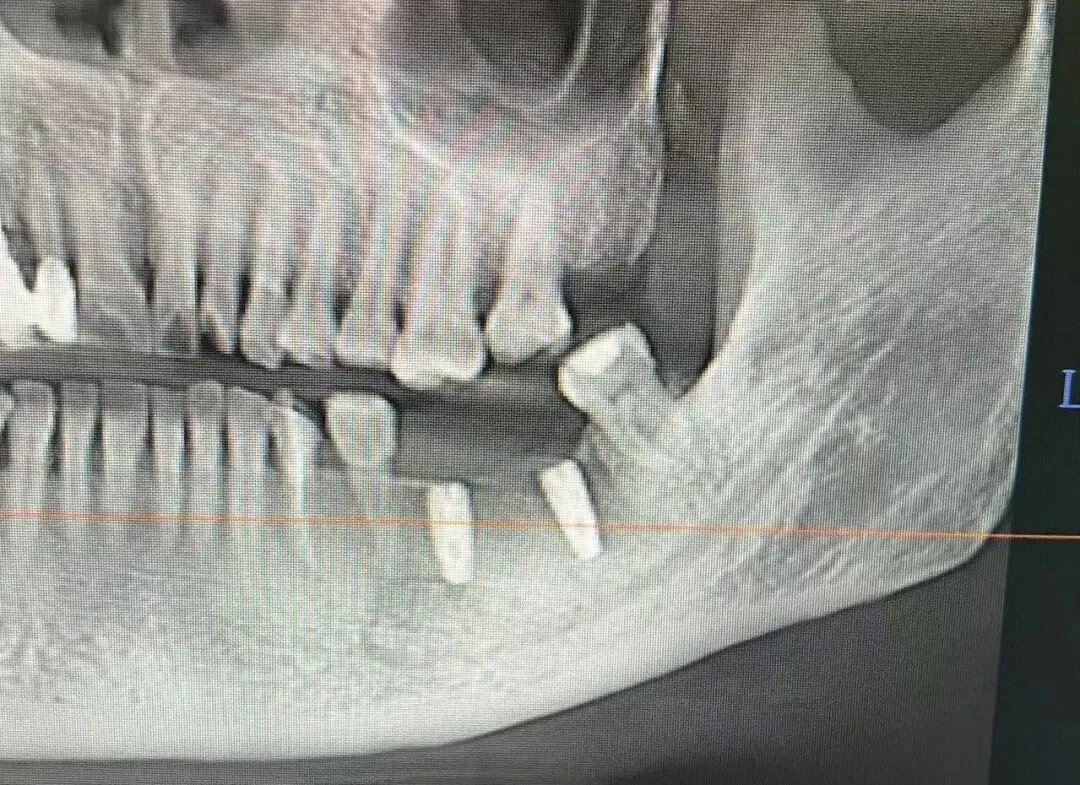

7、种植影像学分析;可以获得骨高度 ,骨宽度信息 ,甚至可以模拟种植体植入位点

六、学员回家后部分病例